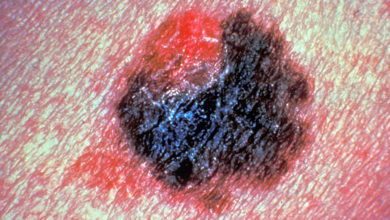

Health United Kingdom95% of Late-Stage Skin Cancer Patients Used to Die – Now More Than Half Survive

A decade ago, only 5% of patients with late-stage melanoma - or skin cancer - would stay alive after five years of being diagnosed. Today, the survival rate has risen to 52% – a significant milestone achieved with the help of two life-saving drugs.